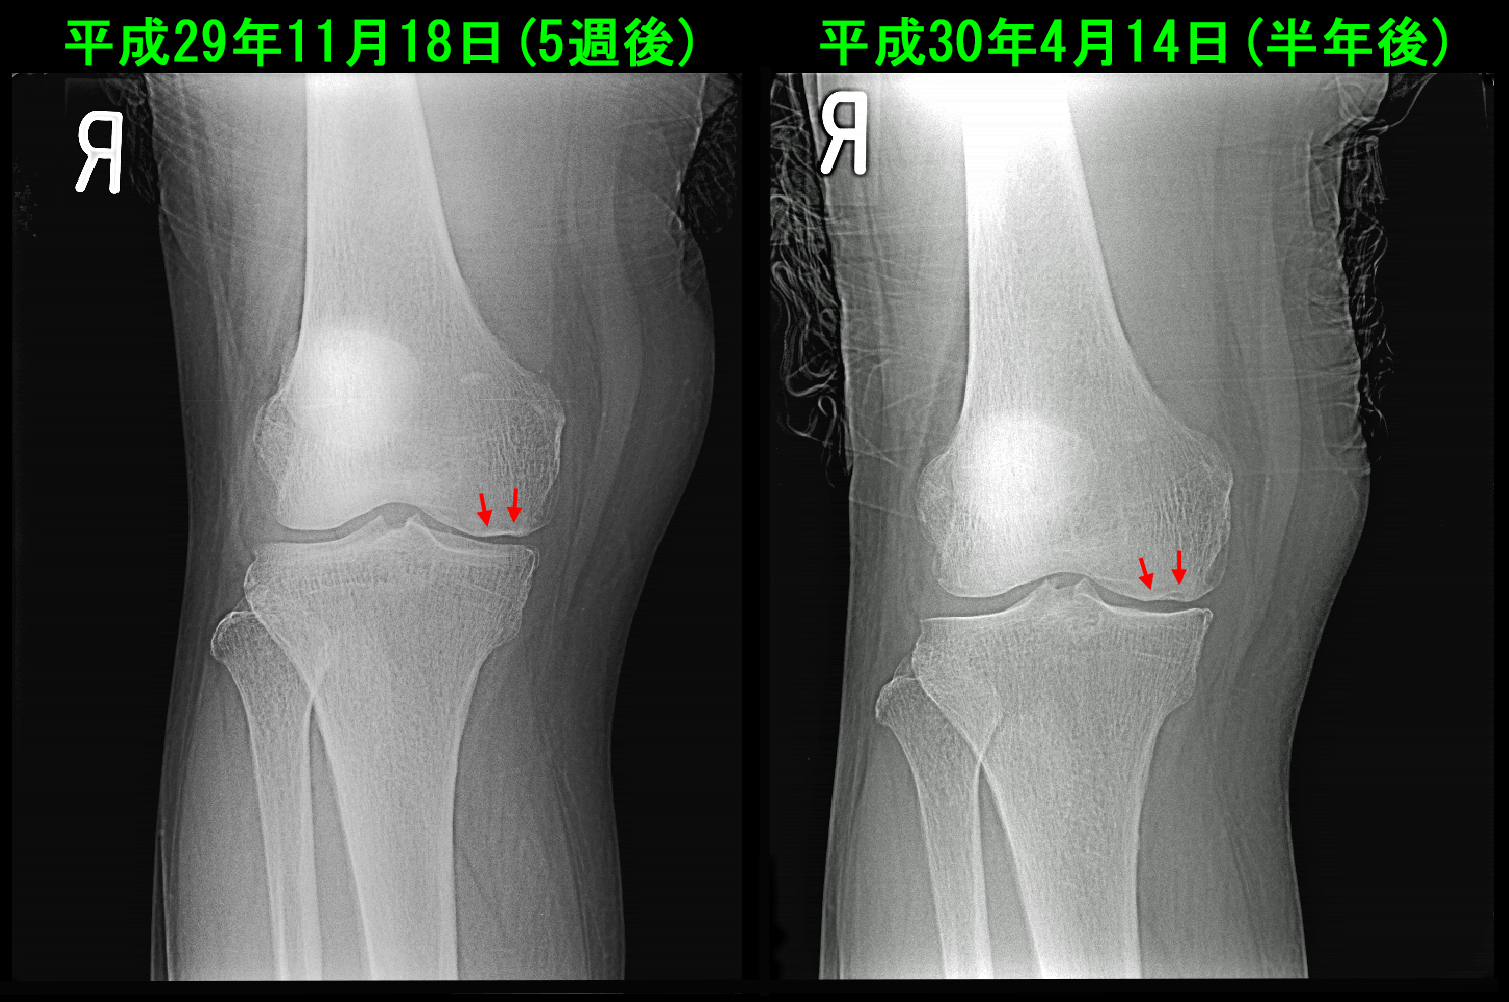

77才女 Xp.jpg

右膝レントゲンでは内側の関節裂隙(すきま)は狭くなっており、中等度の変形性膝関節症の状態です。さらに大腿骨内顆部は一部骨の陥凹を認めます。レントゲン像から大腿骨内顆の骨壊死が発生していることが推察されます。

77才女 MR.jpg

MRI検査では予想通り右大腿骨内顆部に骨壊死が発生していました。さらに右大腿骨内顆部にも小さな骨壊死の所見が確認されます。即ち、令和6年8月に左大腿骨内顆部の骨壊死を発症したのですが、68才女性の患者さんの左膝と同じように小さい骨壊死であったので、比較的短期間(4か月)で左膝痛は痛みなく治癒することになったのだと思います。しかし、右膝の骨壊死は領域が大きく、関節軟骨の摩耗も進行していて中等度の変形性関節症化しているために、左膝のように順調に(4か月程度では)症状の治癒にはならないという経過になっているのです。